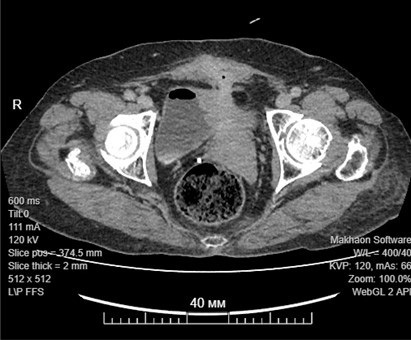

v0x76xКомпьютерная томография зоны прямокишечно-влагалищно-маточно-мочепузырно-кожного свища.В ходе последующего многочасового оперативного вмешательства операционная бригада в составе проректора по лечебной работе ГрГМУ Эдуарда Могилевца, заведующей отделением гнойной хирургии ГрУК Светланы Ждонец и гинеколога Ангелины Горецкой выполнила удаление части толстой кишки, матки с придатками и участком влагалища, участка стенки мочевого пузыря, несущими свищ и участвующими в формировании единой патологической полости; успешно была иссечена кожная часть свища.